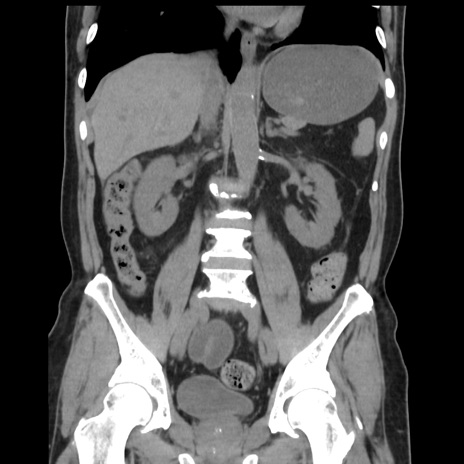

症例16(冠状断像)

【症例】 70歳代男性

【主訴】 腹痛、嘔吐

【現病歴】 約1ヶ月前より間欠的に腹痛と嘔吐あり、当院消化器内科を受診したところCTで多発する肝臓のLDAを指摘され、精査中であった。以降は消化器症状は安定していたが、2日前より嘔気と腹痛があり、同日より排便・排ガスが消失した。改善認めず、 本日、救急外来を受診した。